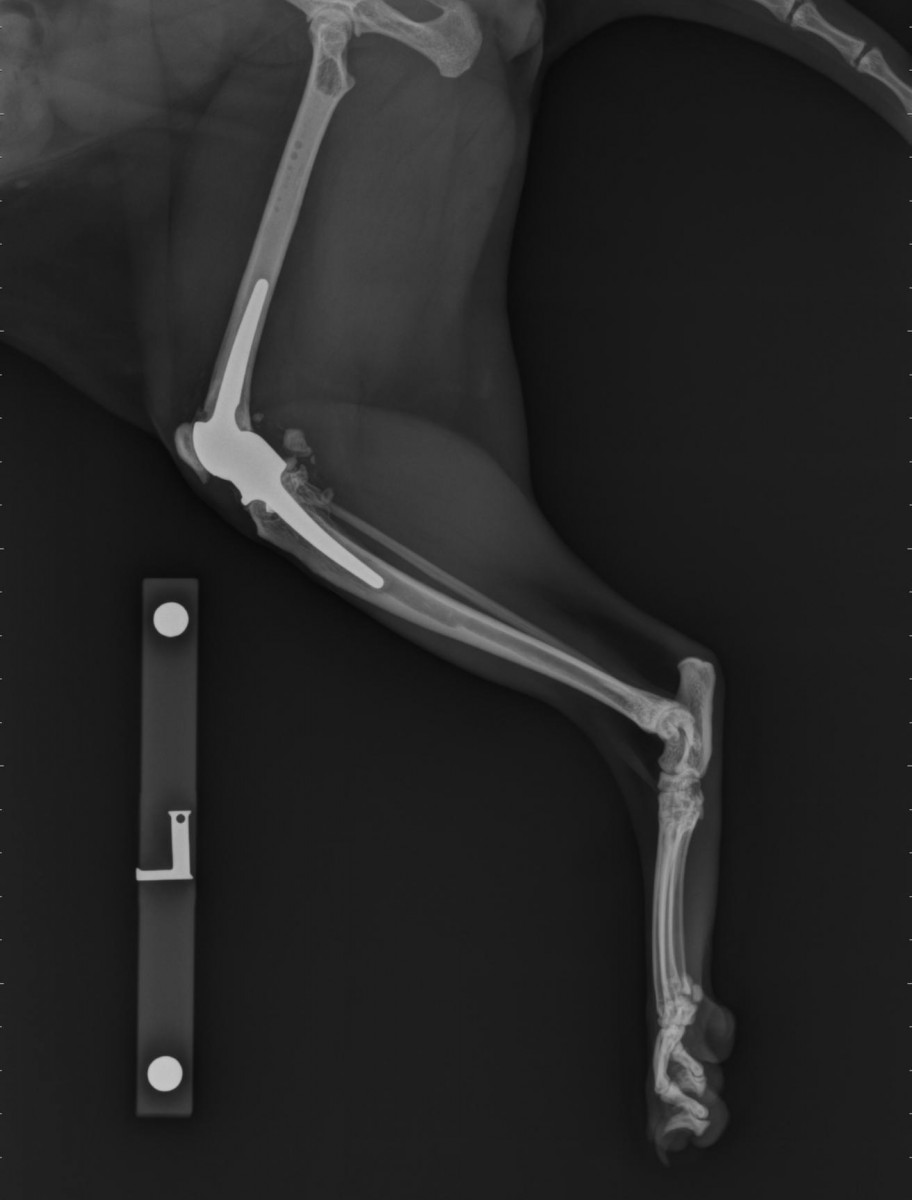

Scan of total knee replacement for Cyrano, the cat. Surgery team led by Cost Of Cat Knee Surgery I think our surgery cost £4.5k. Total knee replacement is reserved for cats that have painful conditions of the knee joint that have proved unresponsive to conventional surgical techniques or conservative management using pain relief. We offer exceptional value, service and care. See the price list for various procedures, from lameness. 47 rows at msm vets we offer a transparent. Cost Of Cat Knee Surgery.

Feline total knee replacement Fitzpatrick Referrals Cost Of Cat Knee Surgery Find out the costs of various procedures and services offered by fitzpatrick referrals, a leading referral hospital for orthopaedic and neurological conditions in pets. See the price list for various procedures, from lameness. I think our surgery cost £4.5k. If you're looking for a referral vet experienced in surgeries such as orthopaedics and soft tissue in northampton, view our prices. Cost Of Cat Knee Surgery.